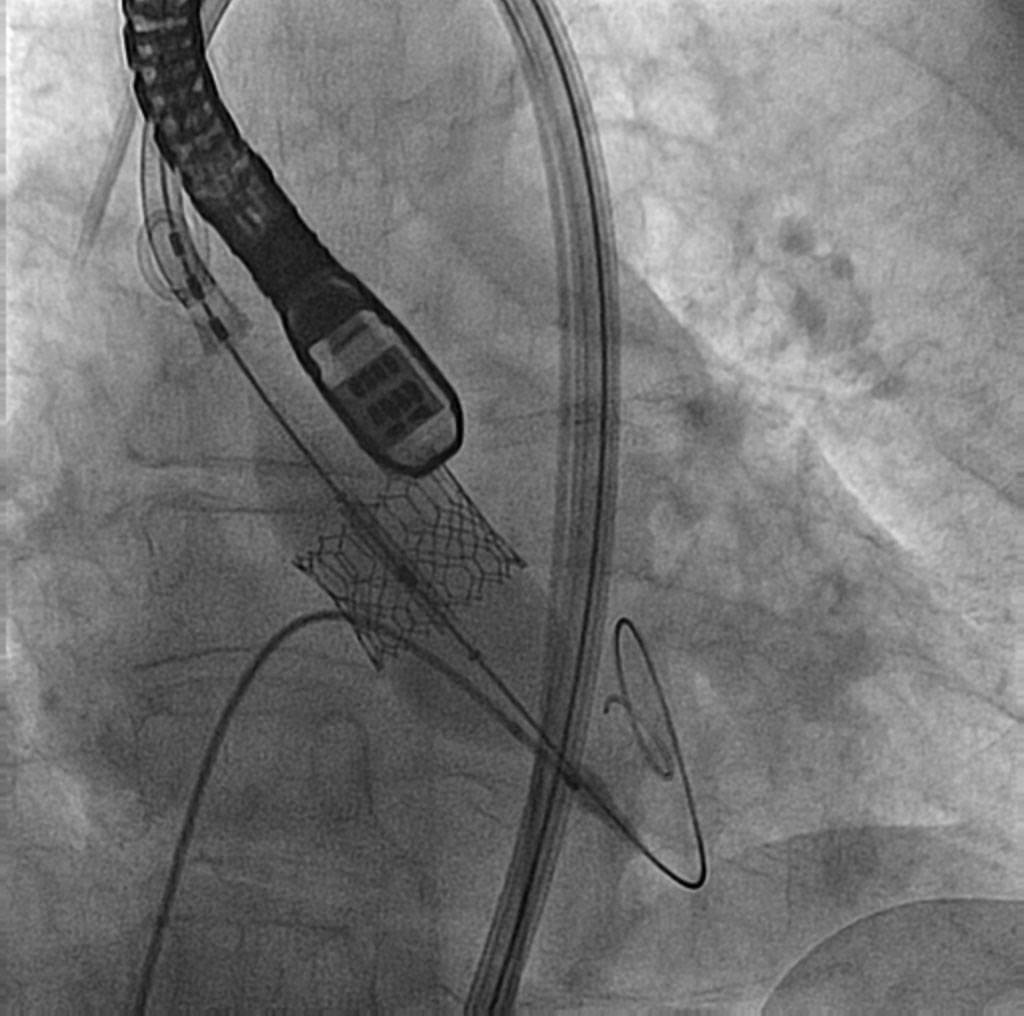

El procedimiento se efectuó bajo anestesia general, mediante abordaje femoral bilateral. Se colocaron 2 catéteres guía Extra Back Up (EBU) de 3,5 mm, de 6 y 7 Fr, en el tronco común izquierdo (técnica ping-pong). Se realizó predilatación secuencial de los ostia coronarios de la descendente anterior y las ramas intermedias mediante un balón de corte de 2,0 mm (vídeo 1 del material adicional) y se implantaron simultáneamente 3 stents farmacoactivos en la descendente anterior (stent liberador de sirolimus, de 2,25 × 15 mm), la primera rama intermedia (stent liberador de zotarolimus, de 2,25 × 18 mm) y la segunda rama intermedia (stent liberador de sirolimus, de 2,25 × 18 mm), por este orden; posteriormente se realizó un inflado simultáneo (figura 2). Por disección retrógrada se implantó un cuarto stent farmacoactivo (stent liberador de zotarolimus, de 4 × 8 mm) en el tronco común izquierdo (figura 3 y vídeo 2 del material adicional), con buen resultado por tomografía de coherencia óptica (figura 4A, B). Inmediatamente después de la intervención coronaria percutánea (ICP) se implantó una válvula aórtica expandible con balón de 23 mm (figura 5 y vídeo 3 del material adicional), también con buen resultado (figura 6 y vídeo 4 del material adicional).

Figura 2. Implante simultáneo de 3 stents farmacoactivos en la descendente anterior y las ramas intermedias.